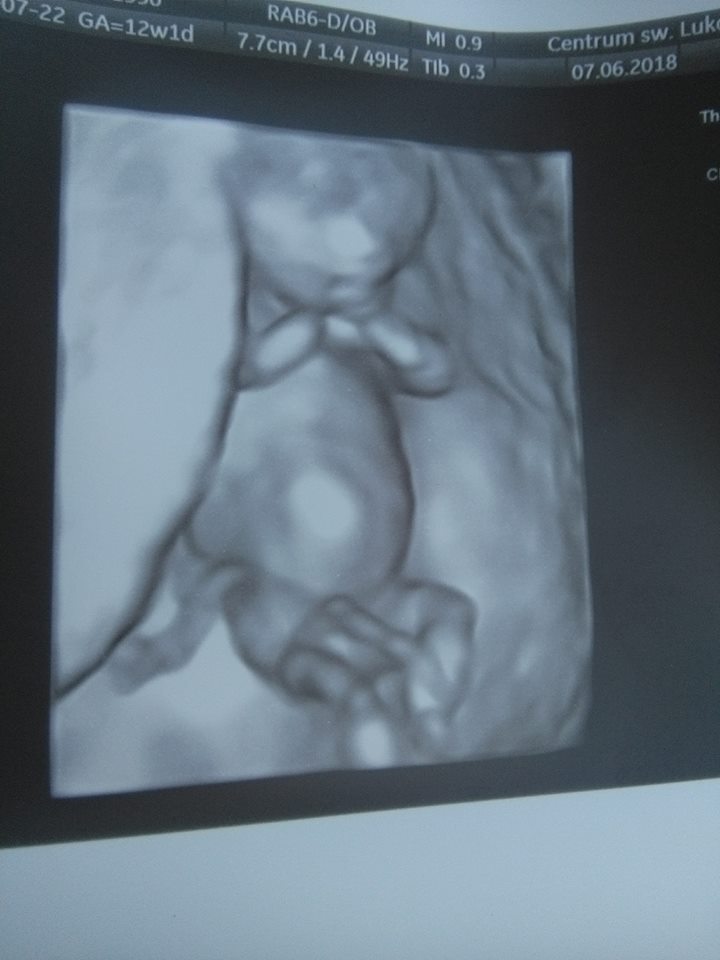

U mnie dzisiaj 12+6. Tak naprawdę to do 20 tygodnia może jeszcze coś urosnąćA w ktorym tygodniu poznalas płeć? Zdumiewajace, ze u takiej kruszynki mozna to dostrzec juz tak wczesnie![]()

Mi powiedzial na prenatalnych, 13+2. Ale tez powiedzial, ze to jeszcze nie pewne na 100%A w ktorym tygodniu poznalas płeć? Zdumiewajace, ze u takiej kruszynki mozna to dostrzec juz tak wczesnie![]()